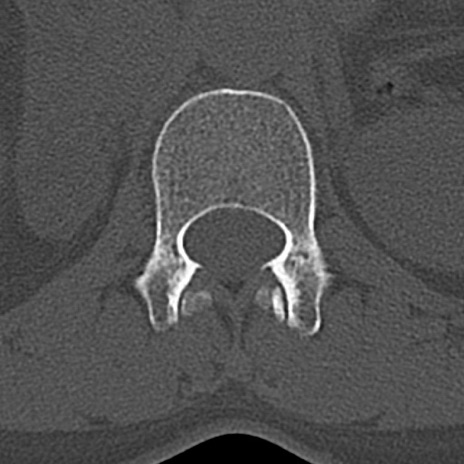

【整形】TIPS症例4 腰椎CT(横断像)

腰椎CT

横断像と矢状断像